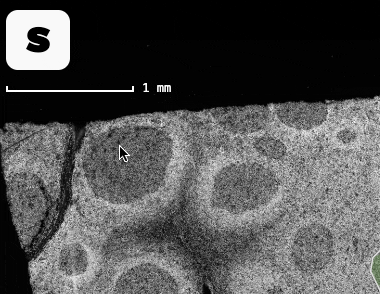

In the summer prototype - which you may remember from the demo video - our image viewer looked like this:

By the end of November, it looks like this: